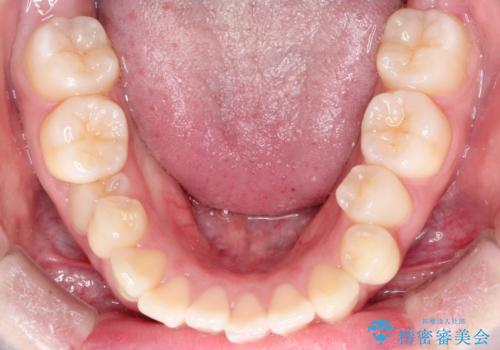

- 4番の歯を4本抜歯をし、上顎にマイクロインプラントを2本埋入し、遠心移動を行いました。

主訴のオープンバイトは改善し、抜歯をしたことで前歯が下がり綺麗になりました。抜歯矯正でしたが1年2か月という短い期間で終了しました。